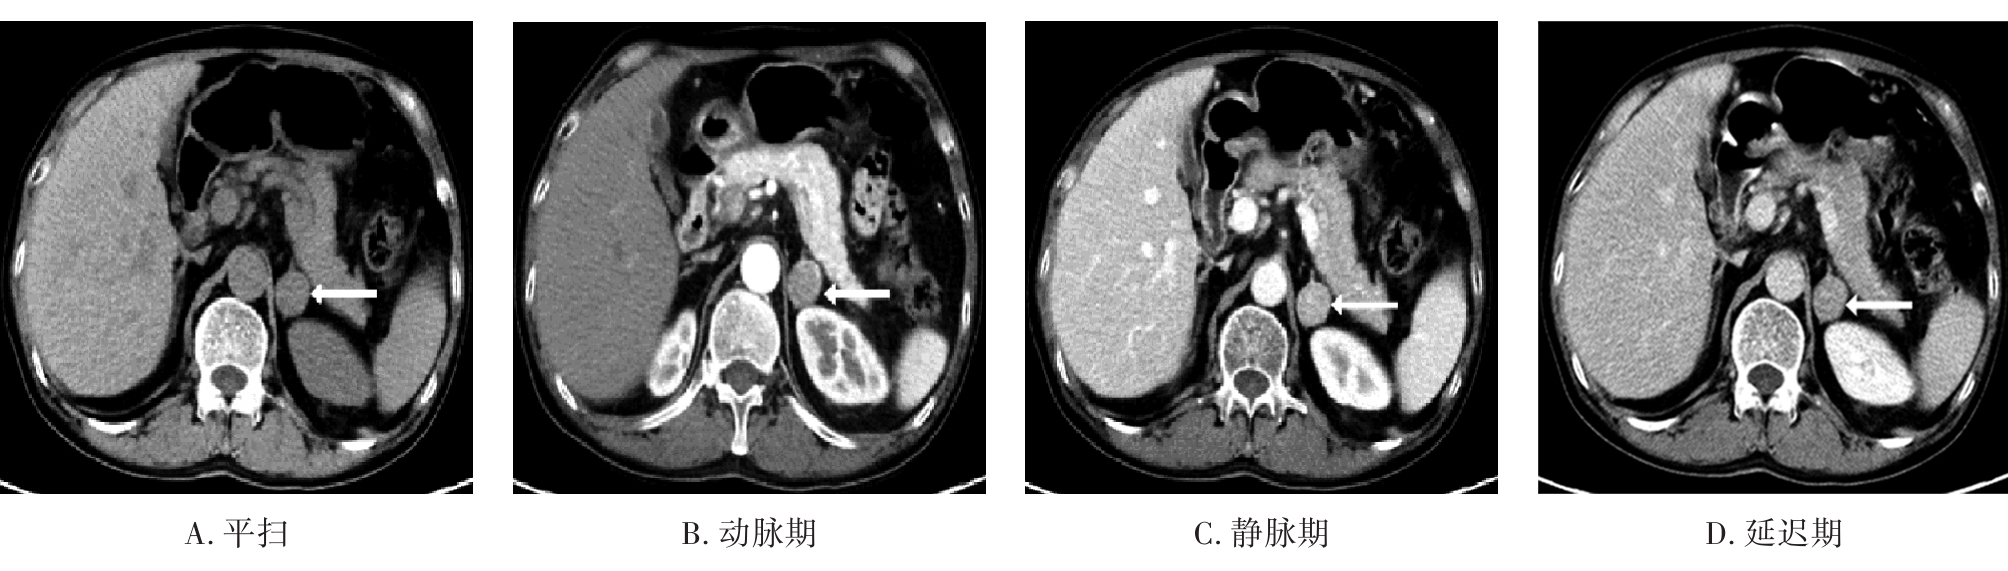

• 嗜铬细胞瘤及副神经节瘤不同生化表型的CT征象对比研究

2024, 49(2):203-209. DOI: 10.13406/j.cnki.cyxb.003433

摘要 (51) HTML (33) PDF 3.10 M (96) 评论 (0) 收藏

摘要:目的 分析生化阴性嗜铬细胞瘤及副神经节瘤(pheochromocytomas and paragangliomas,PPGLs)的电子计算机断层扫描(computed tomography,CT)征象是否有别于生化阳性PPGLs,同时了解生化阳性PPGLs不同表型的CT征象是否存在差异。方法 回顾性分析131例PPGLs患者的术前腹部增强CT图像,包括肿瘤位置、大小、形态、囊变坏死、液-液分层、钙化、向心结节状强化、肿瘤内粗大血管、强化包膜、绝对廓清率及相对廓清率。根据生化水平,将患者分为生化阳性组和阴性组,阳性组进一步分为去甲肾上腺素型、肾上腺素型及多巴胺型。比较各组及各表型间的CT征象差异。结果 相较于生化阴性组,阳性组PPGLs更大(Z=-2.064,P=0.039)、囊变坏死(χ2=6.610,P=0.010)及向心结节状强化(χ2=3.909,P=0.048)的比例更高;相较于去甲肾上腺素型,肾上腺素型PPGLs更大(Z=-2.036,P=0.042)、强化包膜比例更高(χ2=7.242,P=0.007)。结论 肿瘤大小、囊变坏死及向心结节状强化的CT征象有助于术前诊断生化阴性PPGLs,肿瘤大小及强化包膜有助于解释去甲肾上腺素型及肾上腺素型PPGLs不同临床表现产生的机制。